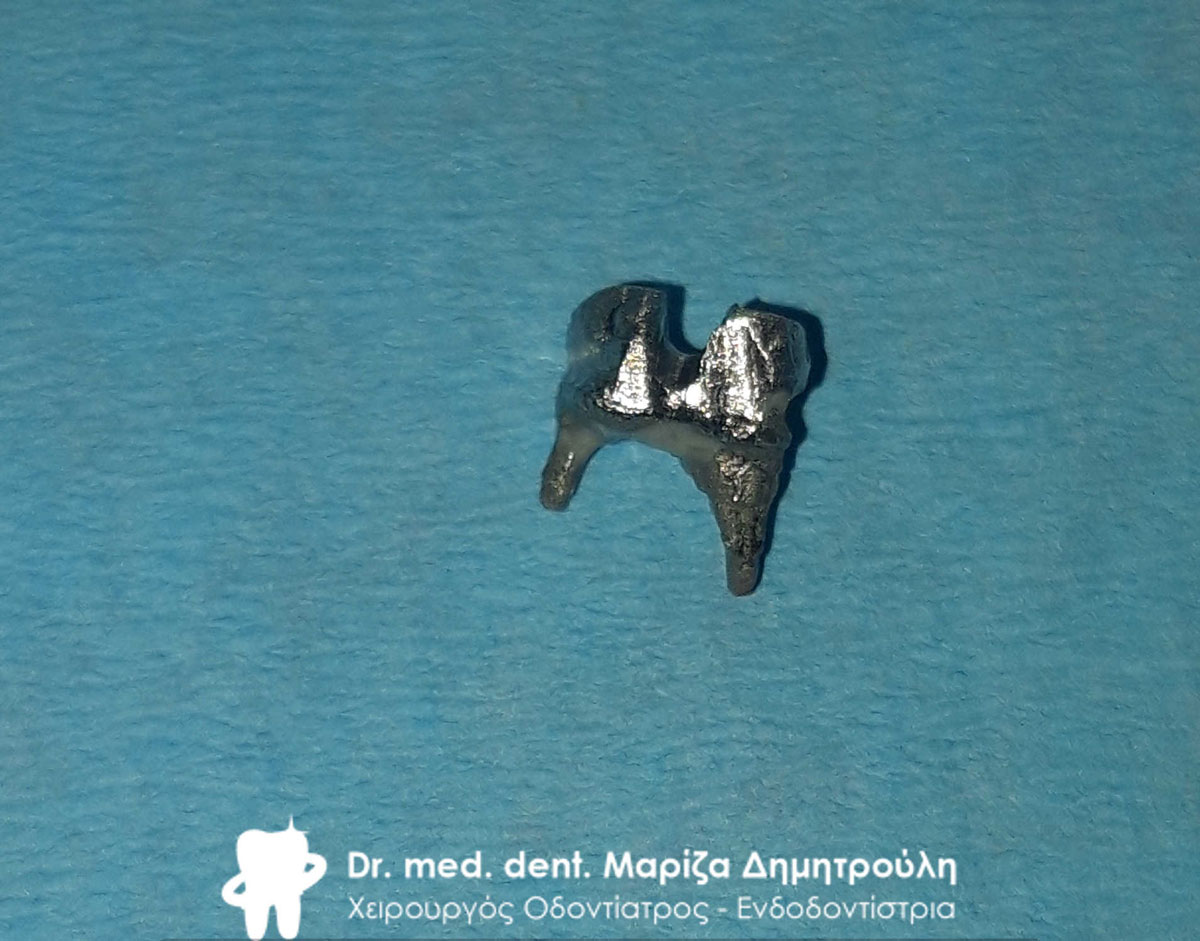

Αφαίρεση του διπλού μεταλλικού άξονα από τον πρώτο γομφίο

Εικόνα της εγγύς ρίζας του πρώτου γομφίου μετά την επανάληψη απονεύρωσης και την αφαίρεση της άπω ρίζας